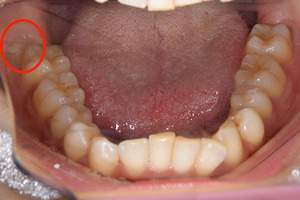

右下の親知らずですが、真横にはえています。お口の中では一部分だけみえています。この状態ですと歯を磨くことが困難で、虫歯になったり、歯ぐきに炎症がおき、腫れて痛みがでるということがあります。

麻布十番歯科で抜歯予定の親知らずの位置を示した口腔内写真

そのため、抜くことをお勧めしていますが、レントゲン写真で、下歯槽神経と親知らずが近接していることが確認できます。